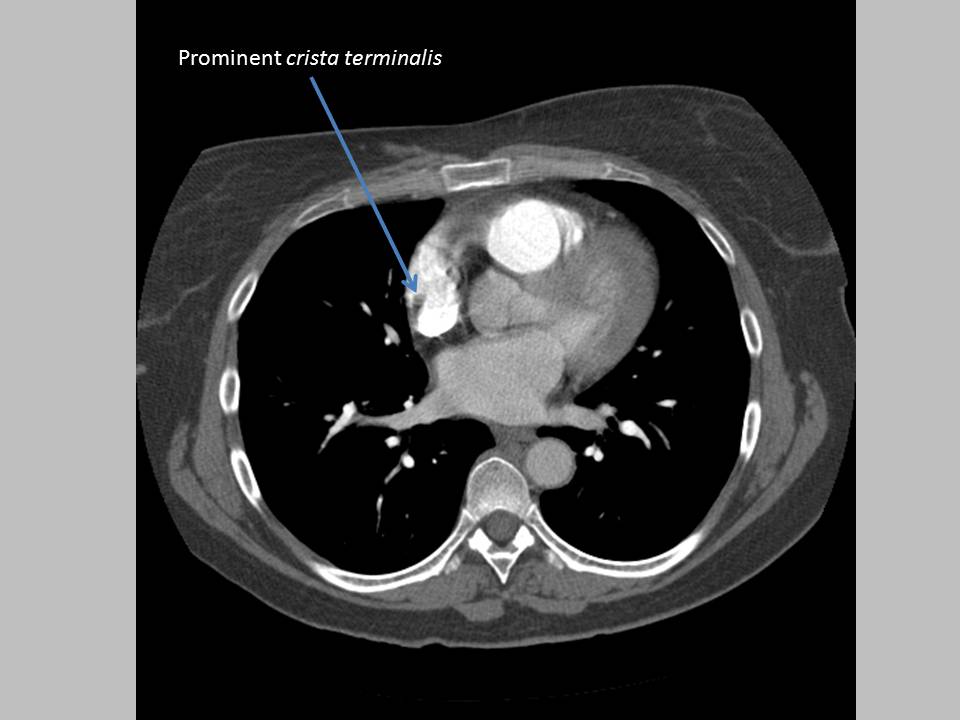

(a) Axial CT angiogram shows a prominent crista terminalis (red arrows Pectinate Muscles And Crista Terminalis Moreover, the crista terminalis marks the site of the right venous valve of the developing heart. Proximal (atrial) to the parietal vestibule is the array of pectinate muscle bundles that connects with the terminal crest (crista terminalis). Where the crista terminalis and the opening of the superior. Coursing between the caval orifices, it divides the pectinate muscle origin and the. Pectinate Muscles And Crista Terminalis.